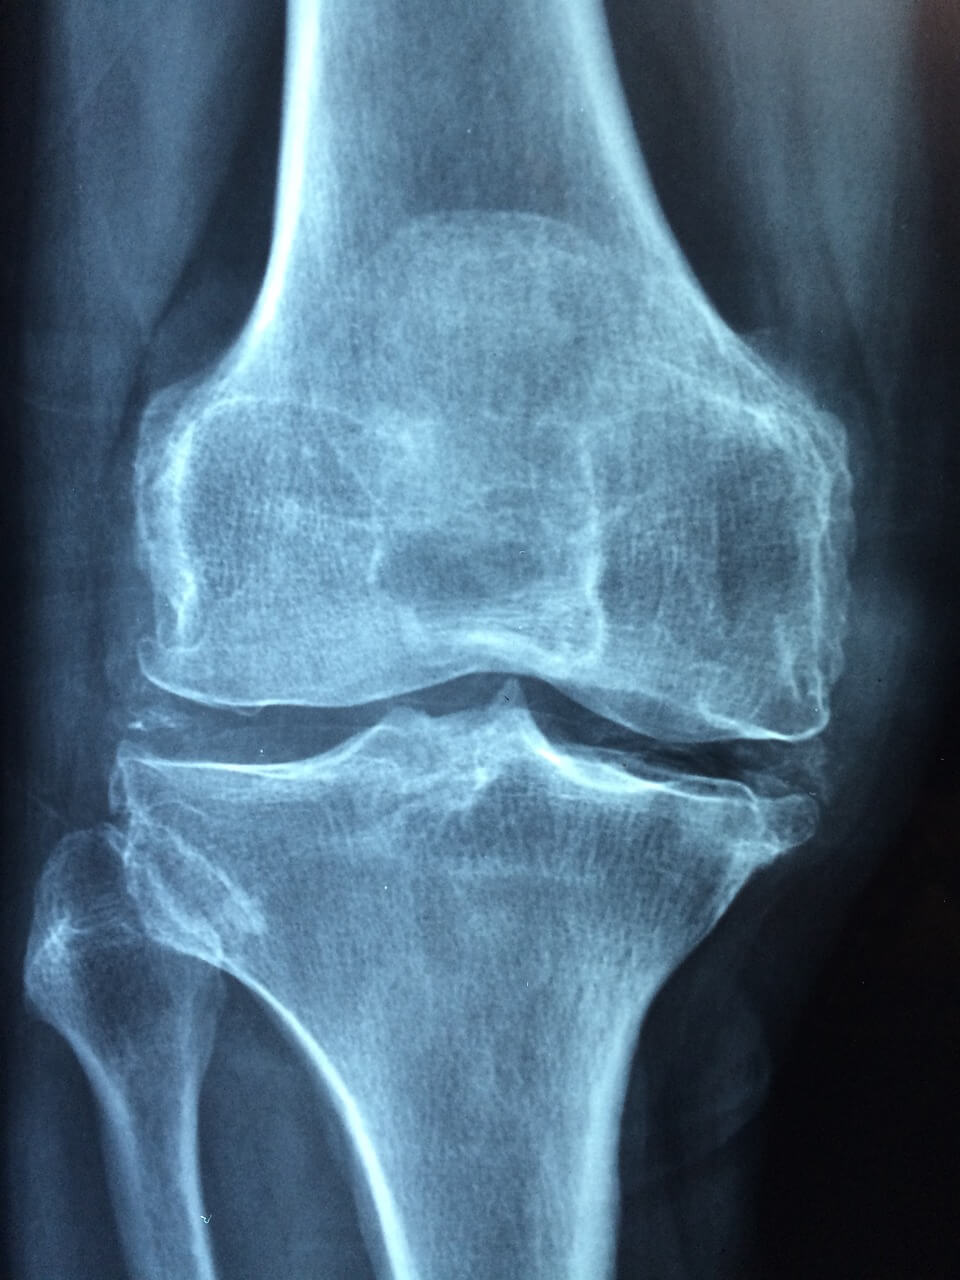

무릎 연골 손상의 증상은 다양할 수 있습니다. 주요 증상으로는 무릎 통증, 무릎 부기, 관절 움직임의 제한, 무릎에서 끈적거리는 느낌 등이 있습니다. 무릎 관절 연골 부근의 통증 증상은 활동 시 더욱 두드러질 수 있으며 불편함이 심하다면 의사와 상담하시는 편이 좋습니다.

무릎 연골 관절과 연골은 시기를 놓치면 회복이 어려운 신체부위로 적절한 시기를 놓치지 않고 치료를 받는 것이 중요합니다. 증상을 꼭 가볍게 여기고 지나치지 마시고 가까운 병원에 방문하셔서 연골이 더이상 손상되지 않도록 조치를 취하시는 걸 권해드립니다.